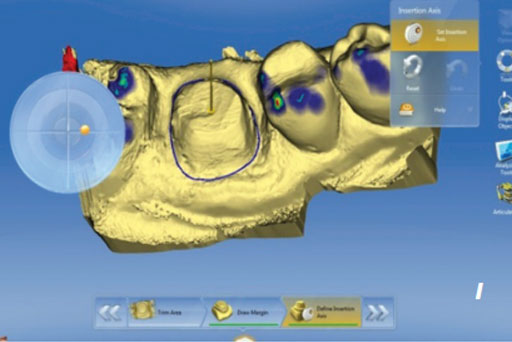

Cerec Dis Hekimliginde Cad Cam Uygulamasi

Sabit Protezler Bolum 9 2 Cad Cam Ve Freze Teknolojisi

Cerec Dis Hekimliginde Cad Cam Uygulamasi